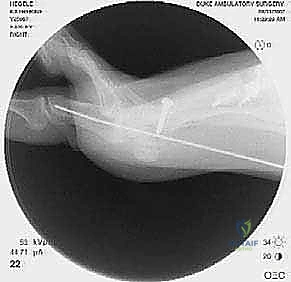

كسور الناتئ المرفقي: دليل شامل للعلاج الجراحي واستعادة وظيفة المرفق مع الأستاذ الدكتور محمد هطيف

اكتشف كل ما يخص كسور الناتئ المرفقي، من التشخيص إلى أحدث تقنيات العلاج الجراحي (أسلاك الشد والصفائح) وإعادة التأهيل، بإشراف الأستاذ الدكتور…